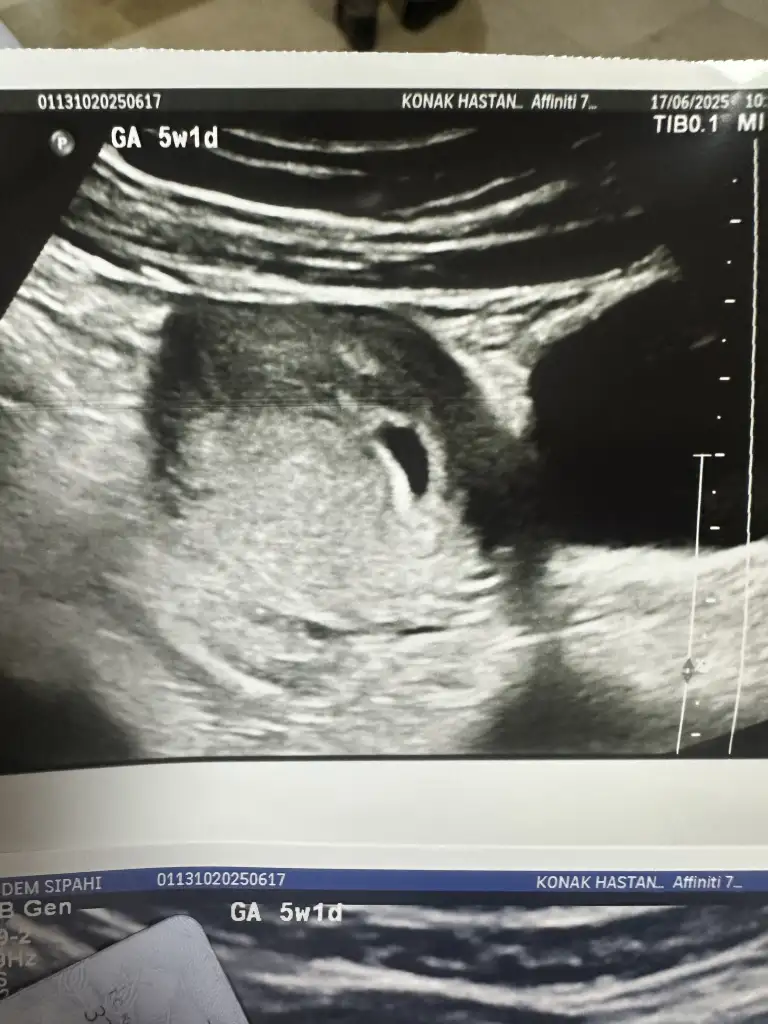

Benimde kalp atışı duyulmadı 10 gün sonra gel dedi 5+1 şuan. Yolk kesesini görüp görmediğini de söylemedi. Ben de sormayı unuttum açıkçası

Fotoğraf verdi mi orda kesenin içine bak minik beyaz bi nokta var mı içinde o yol kesesi kuşum

Kızlar doktor bebek sağa tutunmuş dedi. Kese şekline de bakarak erkek mi kız mı yorum yapabilir misiniz?

Canım inşallah hiçbir sorun yoktur ilk gebeliğim bide biraz zor oldu o yüzden ekstra stresliyim sanırım. Bilmiyorumki keseyi gören herkes erkek dedi ama sağ taraftaydı bu arada

Ya ben hep yusyuvarlak ovalse kız çıkıntılı fasülye gibiydi erkek diyorlar o bilgiyi biliyorum birde chat cbt ye görüntü atar darlardım onu hep

Bende erkek diyorumm :) rahat ol doktorlar bazen sormadıkça bilgi vermiyor maşallah bak herşey yolunda bende ilk muayenede göremedim sonra sorunca söyledi bana bi sonrakilerde,

Ben chat gbt attım. Oval ve uzun gozukuyor. sonlara dogru daraldığı için erkek dedi